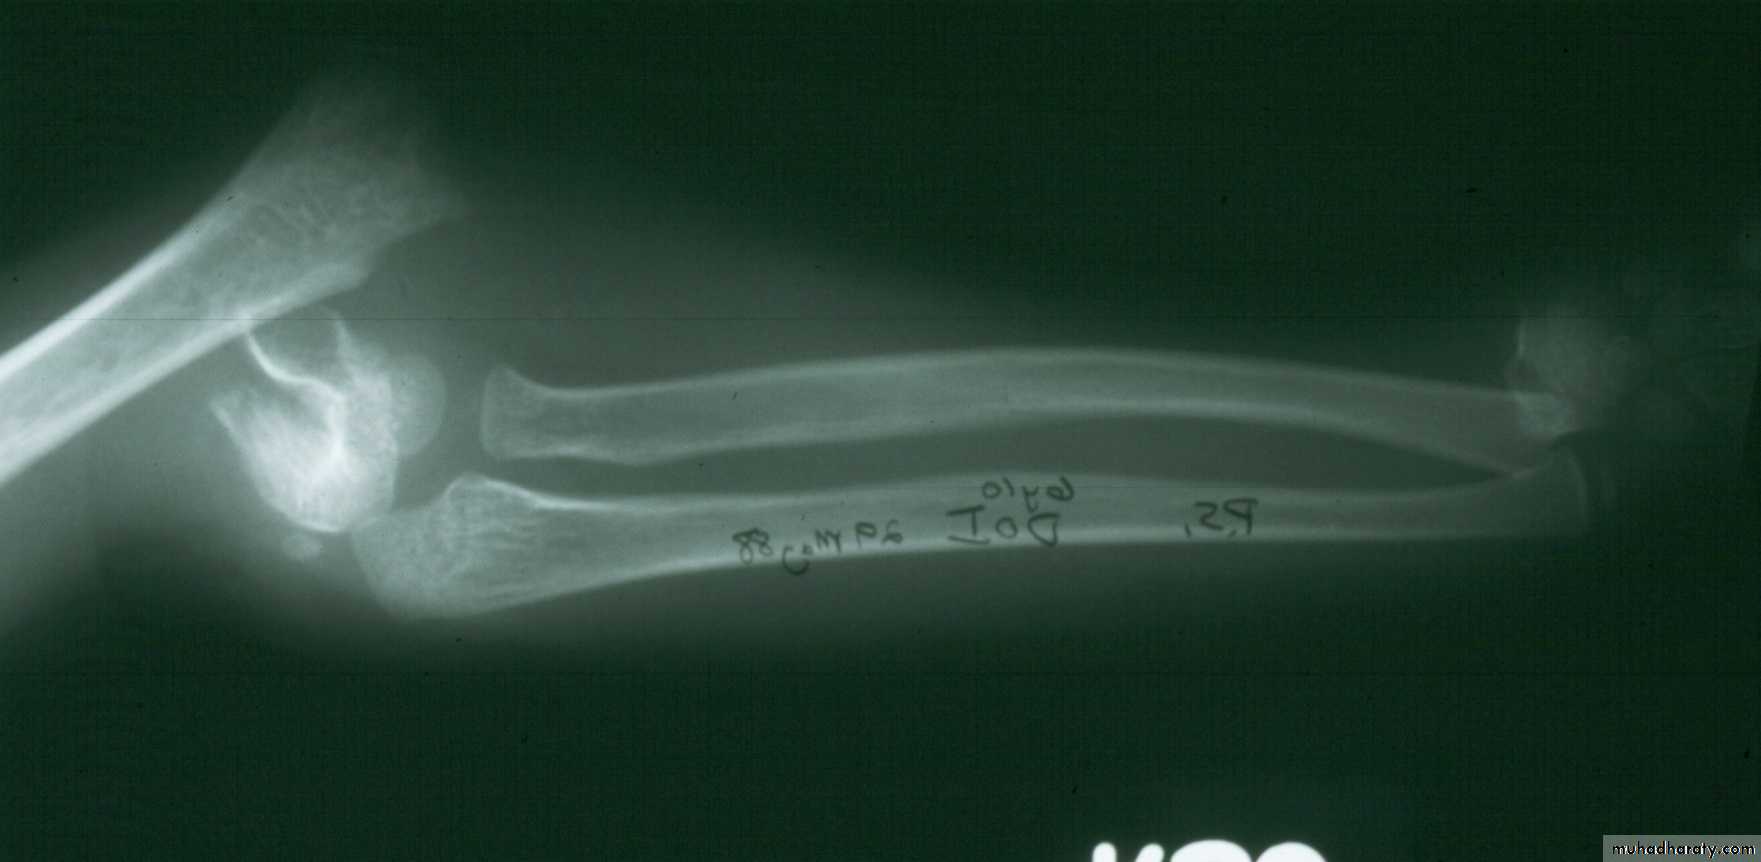

What type of supracondylar fracture

does this patient have?Flex

ionHow do the flexion patterns present?

They present

in the same manner as the extension types.Type I Flexion Injury

This classical Type III pattern

is obviously a flexion injury.With these one needs to be

prepared to do an open reduction !!

8 y.o.

Is this a simple extension

type supracondylar fracture ??

It also has

anterolatateraldisplacement !!

The distal fragment is

not flexed,but also it is not extended to any degree.

This also is a Type III Flexion Pattern.

What is differentabout this fracture?

But, if not recognized as such, it may be a problem.

This fracture was irreducible,

and required an open reduction !!!